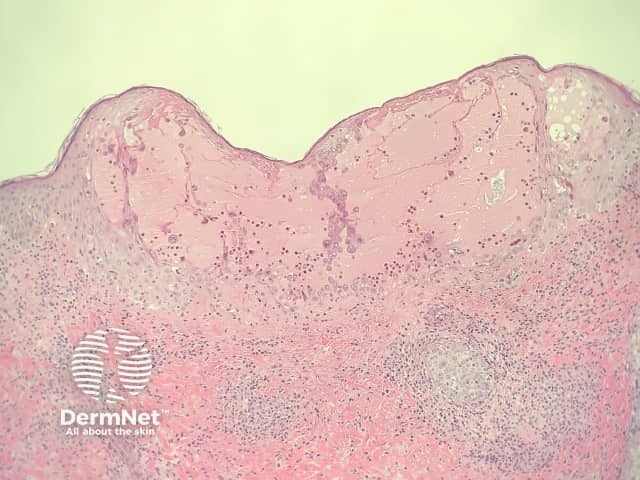

The low power pattern of a typical lesion of chickenpox is an intraepidermal blister (figure 1). The key feature is acantholysis with solitary keratinocytes within the blister cavity. These acantholytic keratinocytes show characteristic viropathic effects: margination of the nuclear chromatin, multinucleation and nuclear inclusions (figures 2,3).

Figure 1